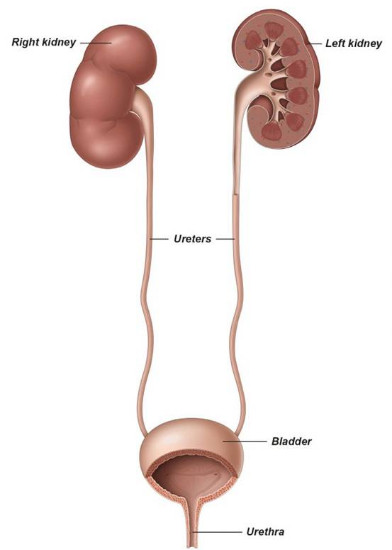

Οι Λίθοι είναι χημικές ενώσεις που σχηματίζονται από την κρυσταλλοποίηση διαφόρων μετάλλων και αλάτων στα ούρα. Μπορούν να επηρεάσουν οποιοδήποτε μέρος του ουροποιητικού μας συστήματος (Εικ. 1), από τους νεφρούς, τους ουρητήρες μέχρι και την ουροδόχο κύστη, και μπορεί να είναι πολύ επώδυνοι. Είναι αρκετά συχνοί, ειδικά σε άτομα ηλικίας 30 έως 60 ετών.

Εικ.1 Το Ουροποιητικό Σύστημα